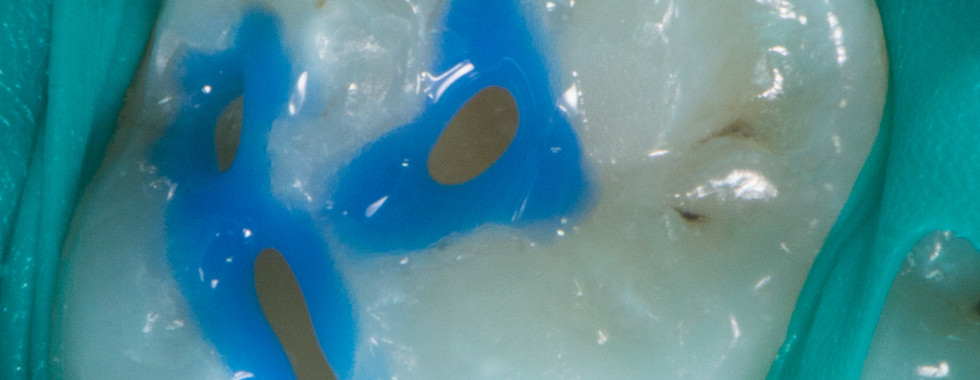

Betäubung & Isolation – Lokalanästhesie bei Bedarf; Kofferdam/Trockenlegung für maximale Haftung.

Adhäsivtechnik & Schichtaufbau – Haftvermittler, Komposit wird in Schichten modelliert und mit Licht ausgehärtet.